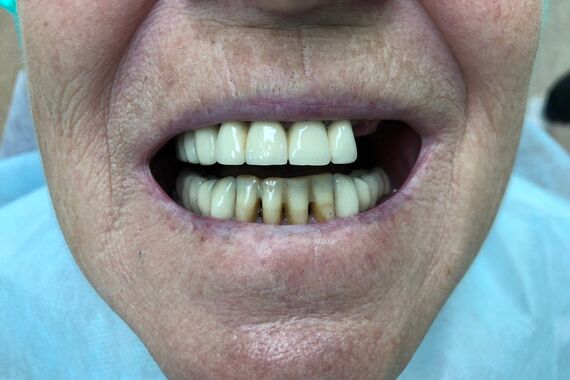

Был достигнут отличный результат, что подтверждается красивой улыбкой благодарной пациентки.